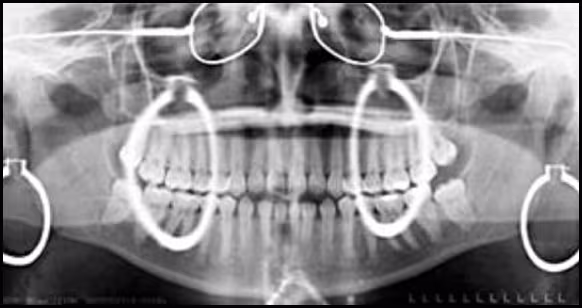

Figure 40. This image illustrates the telltale signs of leaving several metallic objects on the patient – earrings, glasses, and a neck chain. Note the ghosts of the earrings.

First, they produce a radiopaque outline of themselves, usually providing a telltale indication of the error.

Second, they may produce so-called “ghost images.” Ghost imaging is a normal component of the panoramic projection and occurs when an object is penetrated twice by the x-ray beam. Structures or objects that are located posterior to (behind) the center of rotation and the x-ray source tend to be ghosted onto the contralateral side of the image. Ghost images have specific recognizable characteristics that are viewable on the panoramic image.

- The ghost image has the same general shape of the original object but does not produce a mirror image.

- The ghost image appears on the opposite side of the panoramic image compared to the original object.

- The ghost image appears in a higher position on the image than the original object.

- The ghost image appears magnified and unsharp (blurred) more in the vertical plane compared to the original object.